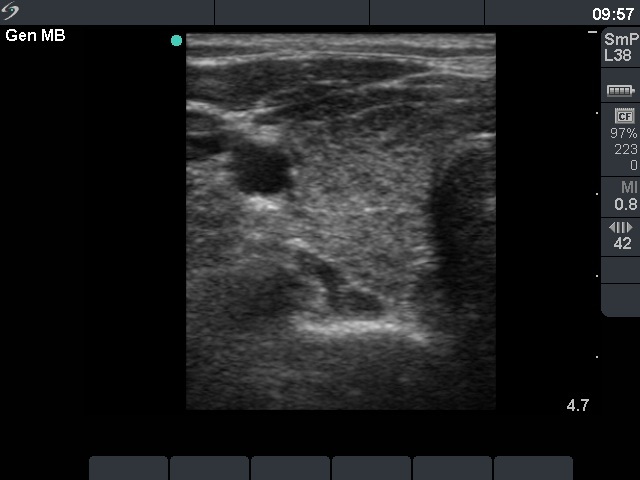

First examination - before surgery (1st row of images)

Clinical presentation: a 47-year-old woman was referred for evaluation of nodular goiter. She noticed a lump in the left lobe for a month.

Palpation: a large nodule in the left lobe.

Results of blood test: euthyroidism (TSH 3.31 mIU/L).

Ultrasonography: the right thyroid was echonormal and contained hypoechogenic areas. The left lobe was moderately hypoechogenic. There was a large hyperechogenic nodule in the left thyroid. The nodule displayed halo sign and type 2 vascular pattern.Cytology resulted in benign lesion.

Final diagnosis. Benign nodule in the left thyroid. Chronic lymphocytic thyroiditis. Left lobectomy was advised because of the size of the nodule.

Histopathology disclosed benign hyperplastic nodule and chronic lymphocytic thyroiditis.